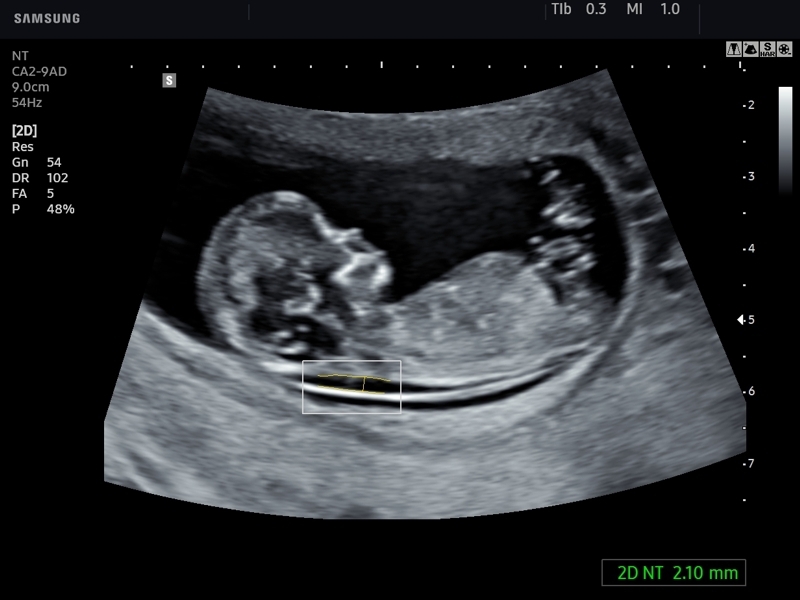

• Модуль 2D NT - полуавтоматическое измерение толщины воротникового пространства (маркер синдрома Дауна).

• Конвексный датчик Samsung Medison CA2-9AD